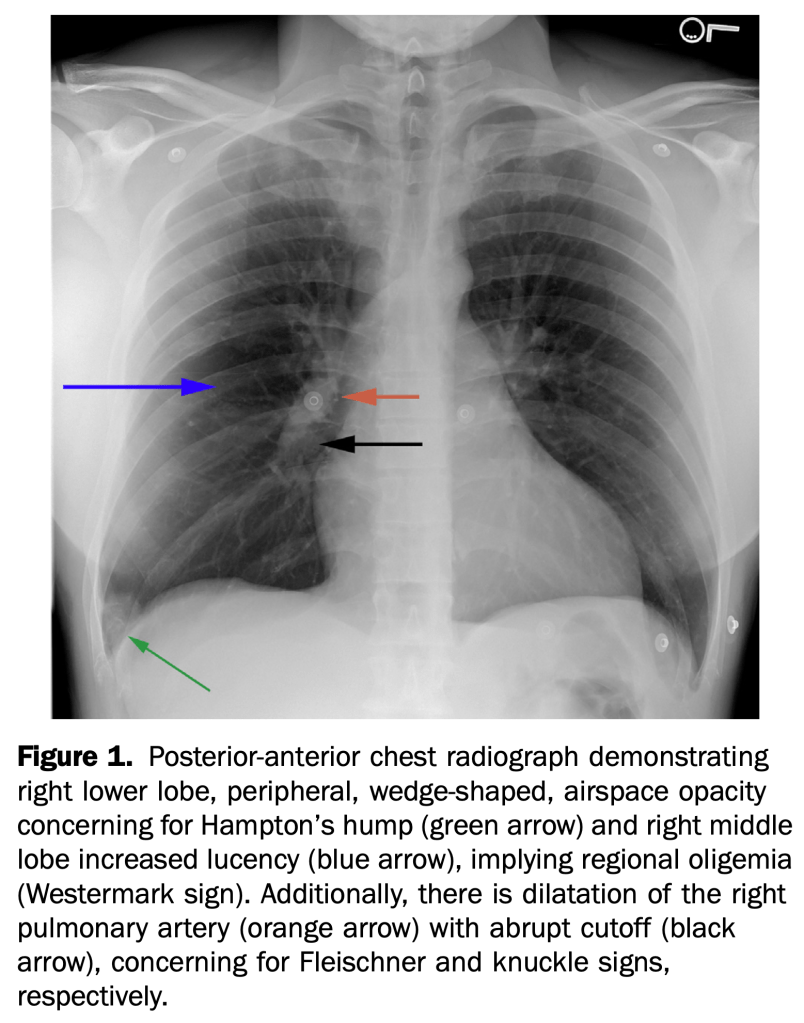

- An otherwise healthy 35-year-old active duty military infantryman presented to the emergency department, complaining of intermittent dyspnea over one-week duration, which was worsened by exertion. He recalled some unusual left leg cramping three weeks before and reported an uncomplicated tooth extraction one week before, but denied any invasive surgeries.

- This case demonstrates multiple rare but specific radiographic findings of pulmonary embolism. These include the Westermark, knuckle, and Fleischner signs, in addition to Hampton’s hump.